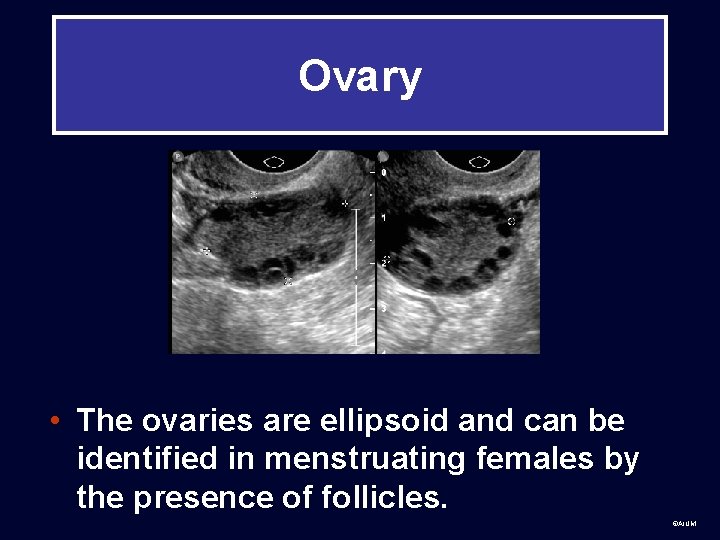

Ovary • The ovaries are ellipsoid and can be identified in menstruating females by the presence of follicles. ©AIUM